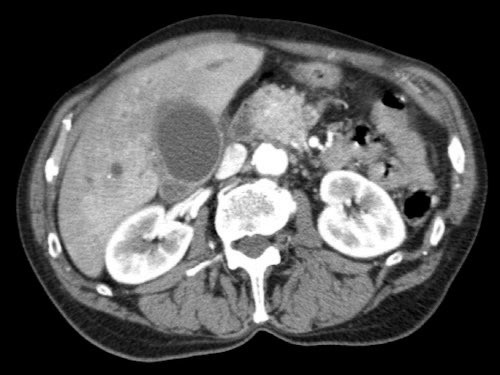

Tái tạo mặt phẳng coronal cho thấy:

- Bất thường bờ viền thành SMV được nhận thấy rõ hơn trên tái tạo coronal này (mũi tên).

- Khối u ở thân tụy (đầu mũi tên trắng).

- Huyết khối trong các nhánh bên của SMV (mũi tên xanh nhỏ).